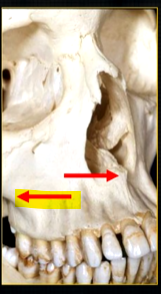

posteriorly, the maxilla….

widens as it articulates with the zygoma or cheekbone

The zygomatic buttress is a key vertical support structure of the midface, formed by the junction of the zygomatic process of the maxilla and the zygomatic bone

bulk/prominence of the zygomatic cheekbone - radiographically this can overly the apical tissues of the upper molar teeth - solid, dense, white shadow

if its hollowed out by the maxillary sinus, it casts a white, radiopaque U shaped shadow - radiolucent centre